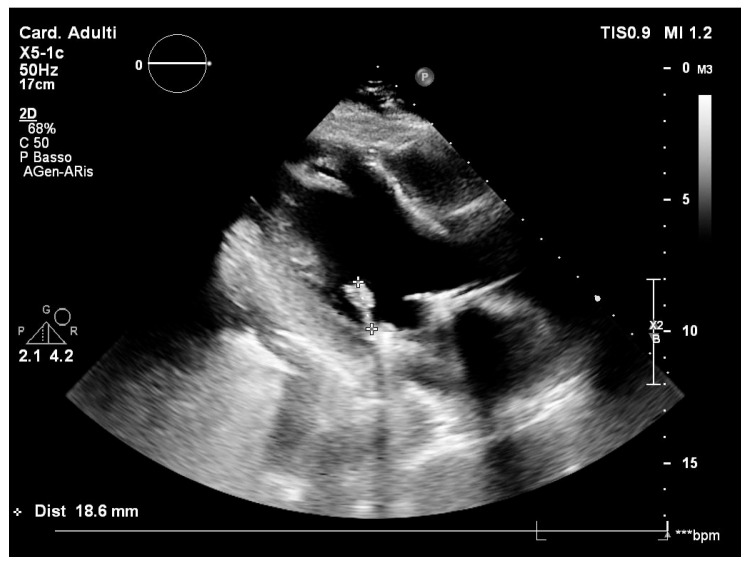

Case report: A 28-year-old male patient was referred to the cardiac surgery unit for urgent mitral valve replacement due to suspicion of infective endocarditis. Microbiological tests yielded negative results. Following recovery and discharge with antimicrobial therapy for 6 weeks, the patient experienced prosthesis detachment, necessitating re-hospitalisation for an emergency valve replacement. Vibrio metschnikovii was identified on the prosthesis valve through PCR and successfully treated with ciprofloxacin. However, a spontaneous rupture of the ascending thoracic aorta led to a neurological injury.